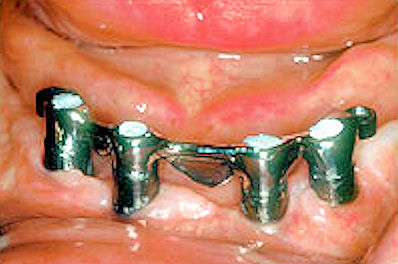

Bar secured to abutment with screws